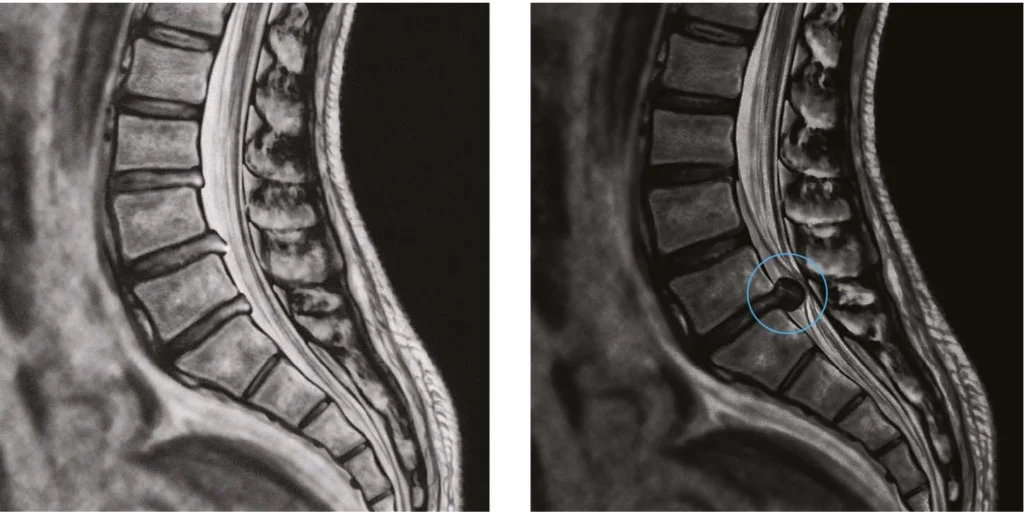

- Ressonância magnética (RM): exame padrão-ouro, que mostra a hérnia e a compressão do nervo.

- Interlaminar: mais utilizada para hérnias em níveis mais baixos (L4-L5 e L5-S1). O acesso é feito pela parte posterior da coluna.

- Transforaminal: indicada para hérnias em níveis mais altos (L1-L4) ou em posição lateral. O acesso é feito pela lateral da coluna, através de uma área chamada triângulo de Kambin.